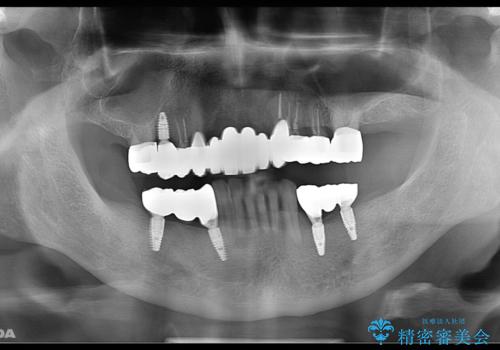

まずは歯周病の治療と抜くしかない歯を抜き、インプラント治療とセラミック治療を行いました。

治療中でも見た目が問題ない様に仮歯を製作していきますが、今回は奥歯に仮歯を入れることが不可能であったため、インプラントが使用できるまでの半年間は入れ歯を使用して頂きました。